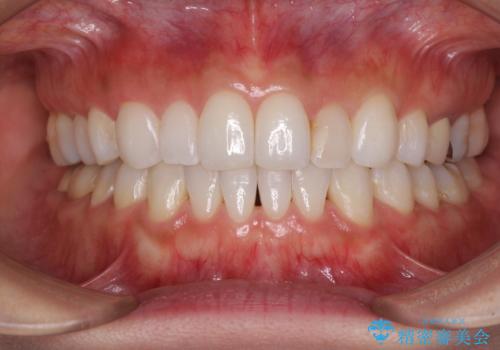

咬合平面の乱れを改善(全顎矯正歯科治療)

治療途中で体調を崩してしまったため、インプラント治療からブリッジによる補綴治療へ切り替え、矯正治療も早めの1年で装置を外しました。

下に降りていた左上の大臼歯が本来の位置に動き、かみ合わせが大変安定し、患者様には大変満足していただけました。